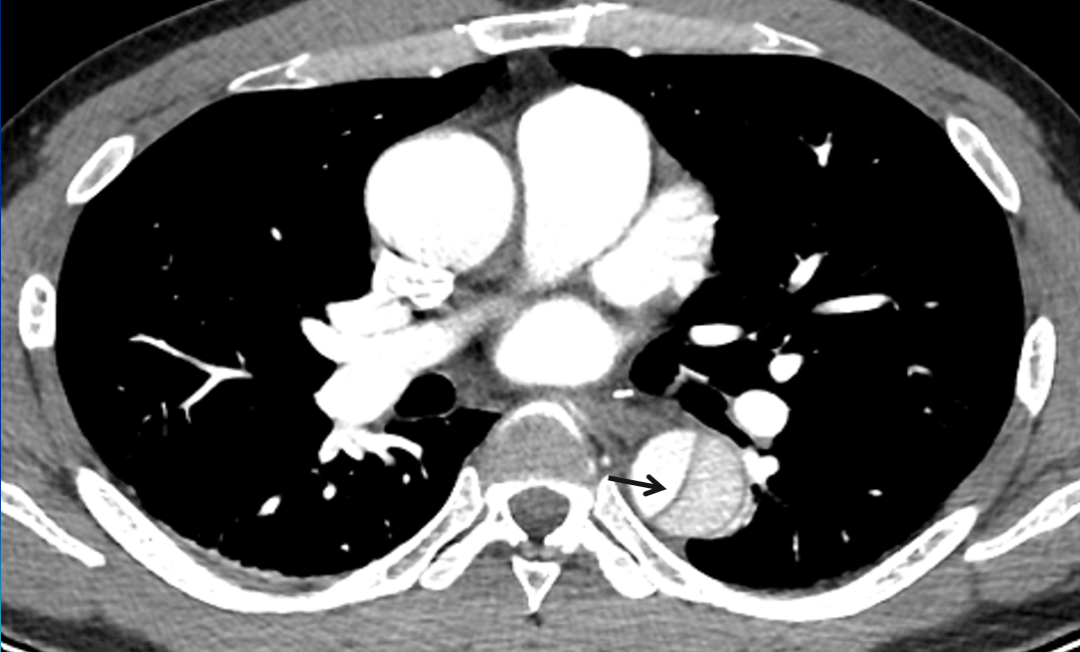

患者,男,40岁。主诉:胸痛1小时入院,无呼吸困难及咳血症状,休息后无缓解,有放射至后背,有高血压病史,D-二聚体0.347mg/l ↑。主动脉CTA血管成像表现如下:

增强薄层CT图像清晰显示撕裂的内膜,表现为弯曲的线样低密度影。(黑箭)